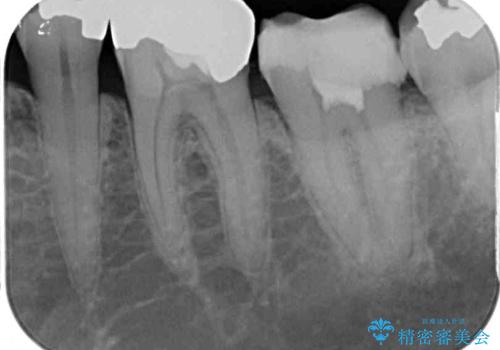

- 痛みを感じ近医を受診したものの、違和感が改善しないとのことで来院された患者様です。

診査をしたところ、神経組織に炎症及ぼすような大きなむし歯があることが分かりました。

虫歯が歯髄腔(神経の部屋)に達している可能性が非常に高かったため、炎症を起こしている神経組織を部分的に切除し、歯根部分の神経組織を保存する治療法が望ましいと考えられました。

神経組織を部分的に除去することが分かっていたため、ラバーダムなどの環境を整え、無菌的環境下にて処置を進めて行きました。

虫歯は深くまで進行しており、歯冠部の神経から出血が認められました。神経を部分的に除去したところ出血が治まったので、生体親和性の非常に高いセメントにて充填し、仮封をしました。

後日状態を確認したところ、残された神経に異常は認められませんでした。